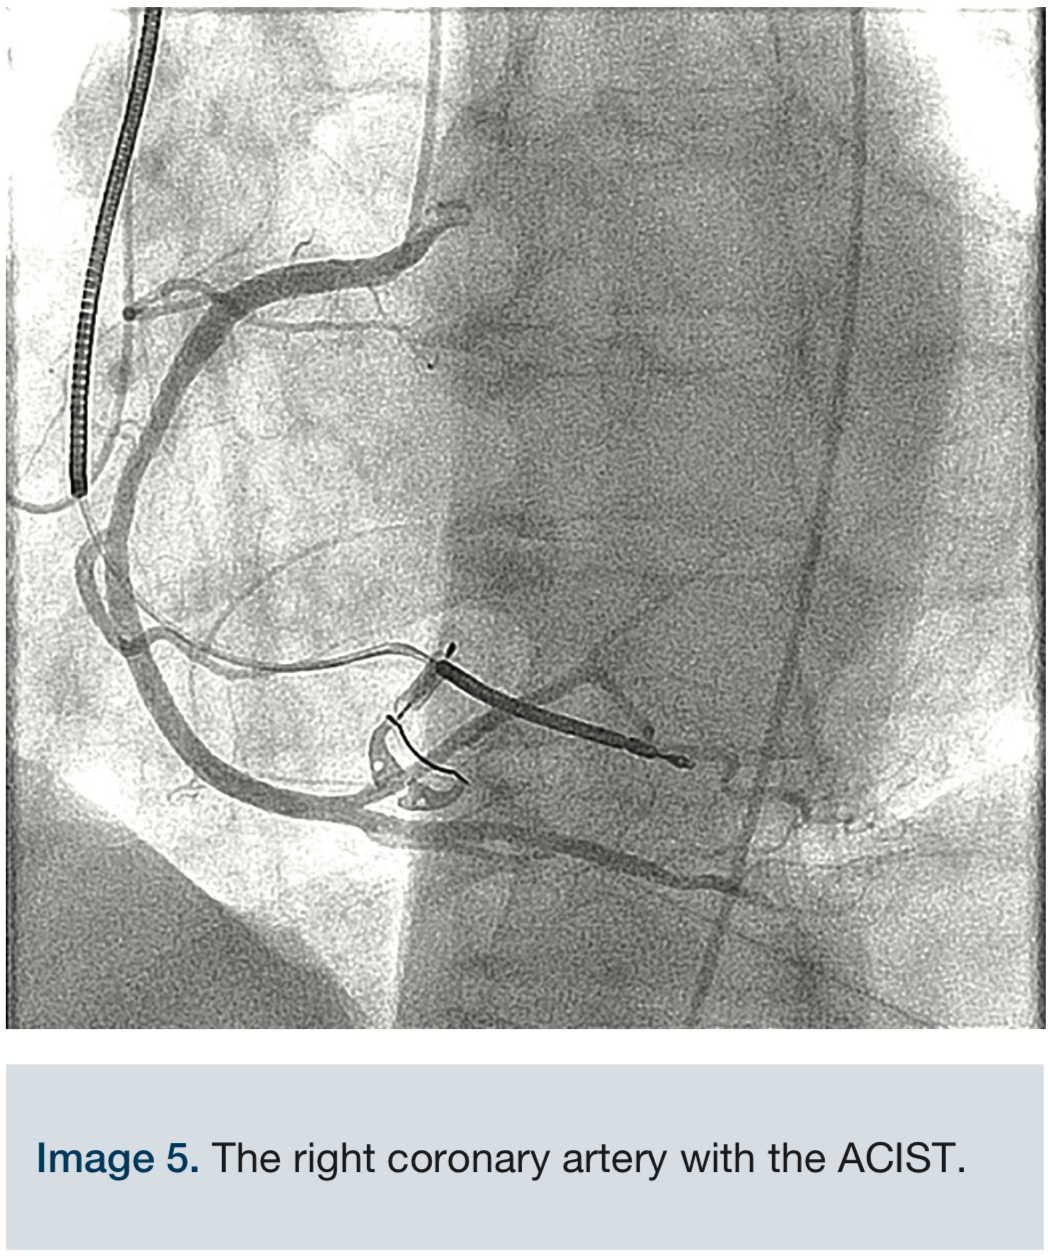

Acist Cvi. * ACIST CVI ANGIOGRAPHI INJECTION ACIST CVi is the contrast injector for: Interventional cardiologists who want to regulate contrast injection flow and minimize risk of CI-AKI—also referred to as contrast induced nephropathy (CIN); Hospital administrators interested in cost containment through cath lab safety and efficiency and reducing potential patient post-procedure adverse events The ACIST | CVi™ Contrast Delivery System (CVi system) is not intended for use as a long-term infusion pump

ACIST CVi is the contrast injector for: Interventional cardiologists who want to regulate contrast injection flow and minimize risk of CI-AKI—also referred to as contrast induced nephropathy (CIN); Hospital administrators interested in cost containment through cath lab safety and efficiency and reducing potential patient post-procedure adverse events The ACIST | CVi® Contrast Delivery System is to be used only by and under quasi-continuous supervision of trained health care professionals in an appropriate licensed health care facility, in a room designated for radiological procedures that involve intravascular administration of a contrast agent

The ACIST | CVi™ Contrast Delivery System (CVi system) is not intended for use as a long-term infusion pump The ACIST CVi system is designed and built to streamline procedures and deliver faster case turnaround, while minimizing the use of contrast 901479-002,01 2019-08 ACIST | CVi Contrast Delivery System User's Guide | 7 1 Introduction The ACIST| CVi® Contrast Delivery System is intended to be used for the controlled infusion of radiopaque contrast media for angiographic procedures